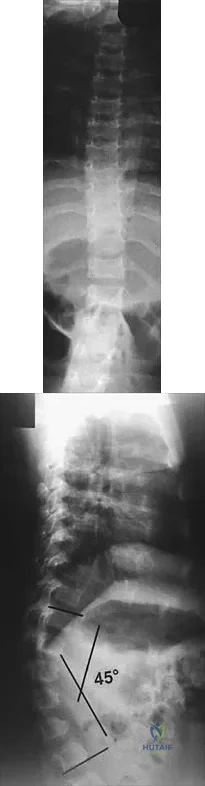

Figures 9a and 9b show the spinal radiographs of a 3-year-old child with short limb dwarfism. The lateral radiograph is obtained with maximal lumbar extension. Management should consist of

Explanation